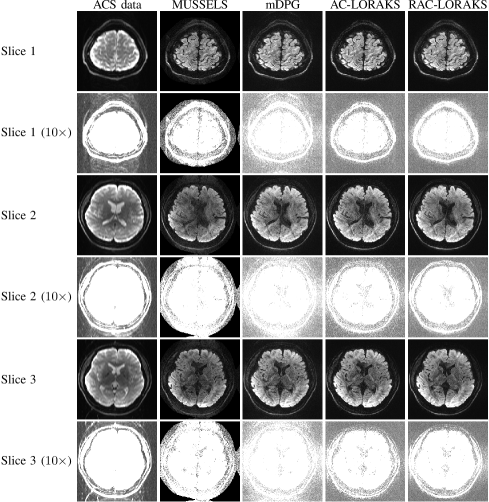

Figure 6 shows reconstruction results from the first set of in vivo diffusion EPI brain data, including a intensity amplification to highlight the ghost characteristics. As can be seen, the ACS data has ghost artifacts in all cases, and both MUSSELS and mDPG reconstructions also exhibit unsuppressed ghosting artifacts. On the other hand, both AC-LORAKS and RAC-LORAKS are relatively ghost-free in this example and have only minor differences from one another (it might be argued that the RAC-LORAKS result has a slightly less-noisy appearance than the AC-LORAKS result, but if so, this difference is very subtle). While this result does not demonstrate an obvious advantage for RAC-LORAKS over AC-LORAKS, it should be observed that this diffusion result is at least consistent with the previous gradient-echo EPI data results, in which we also did not observe a substantial difference between RAC-LORAKS and AC-LORAKS when . In addition, this case involves a very substantial contrast difference between the ACS data and the EPI data. This difference does not appear to have adversely affected the performance characteristics of these methods in substantial ways.

Figure 6: ACS data and reconstruction results for three representative slices from in vivo diffusion brain data (). A 10 intensity amplification is also shown for each slice to better highlight the ghosting characteristics.